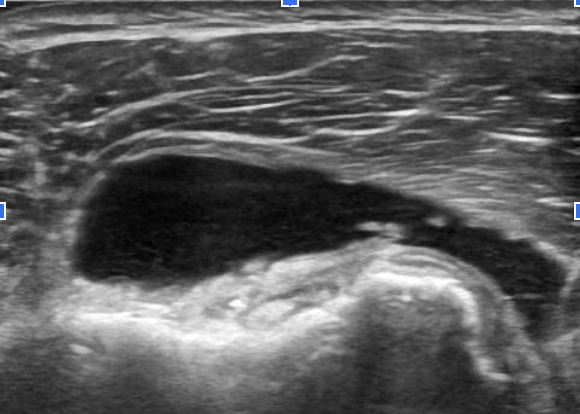

超音波検査について

リウマチ科領域では超音波診断の有用性が認識され、日常診療でも広く普及しつつあります。リウマチ性多発筋痛症においても超音波検査を用いた診断を実践していますが、多くの画像所見は特徴的ではあっても疾患特異的(すなわち確定診断の根拠となる)所見ではないため、症状を有する部位の観察のみで診断が得られることはまずありません。

他の疾患を正しく鑑別するためには、

- 症状を有する部位以外の画像所見の評価

- 他の臨床情報も十分加味

- 必要に応じて関節穿刺を行い貯留した液体の評価